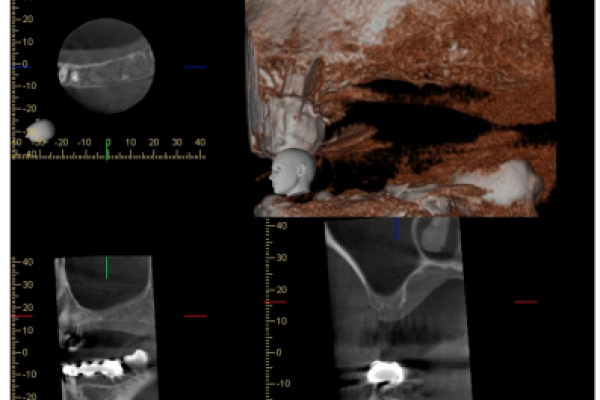

Dos trabajos corresponden a casos clínicos: el de Hernando Calzado y cols. trata sobre la utilización de betafosfato tricálcico en la elevación de seno previa a la colocación de implantes; y Anitua presenta la rehabilitación de un caso con gran atrofia ósea en el maxilar mediante la combinación de dos técnicas quirúrgicas (un injerto en bloque con la técnica de split en dos fases).